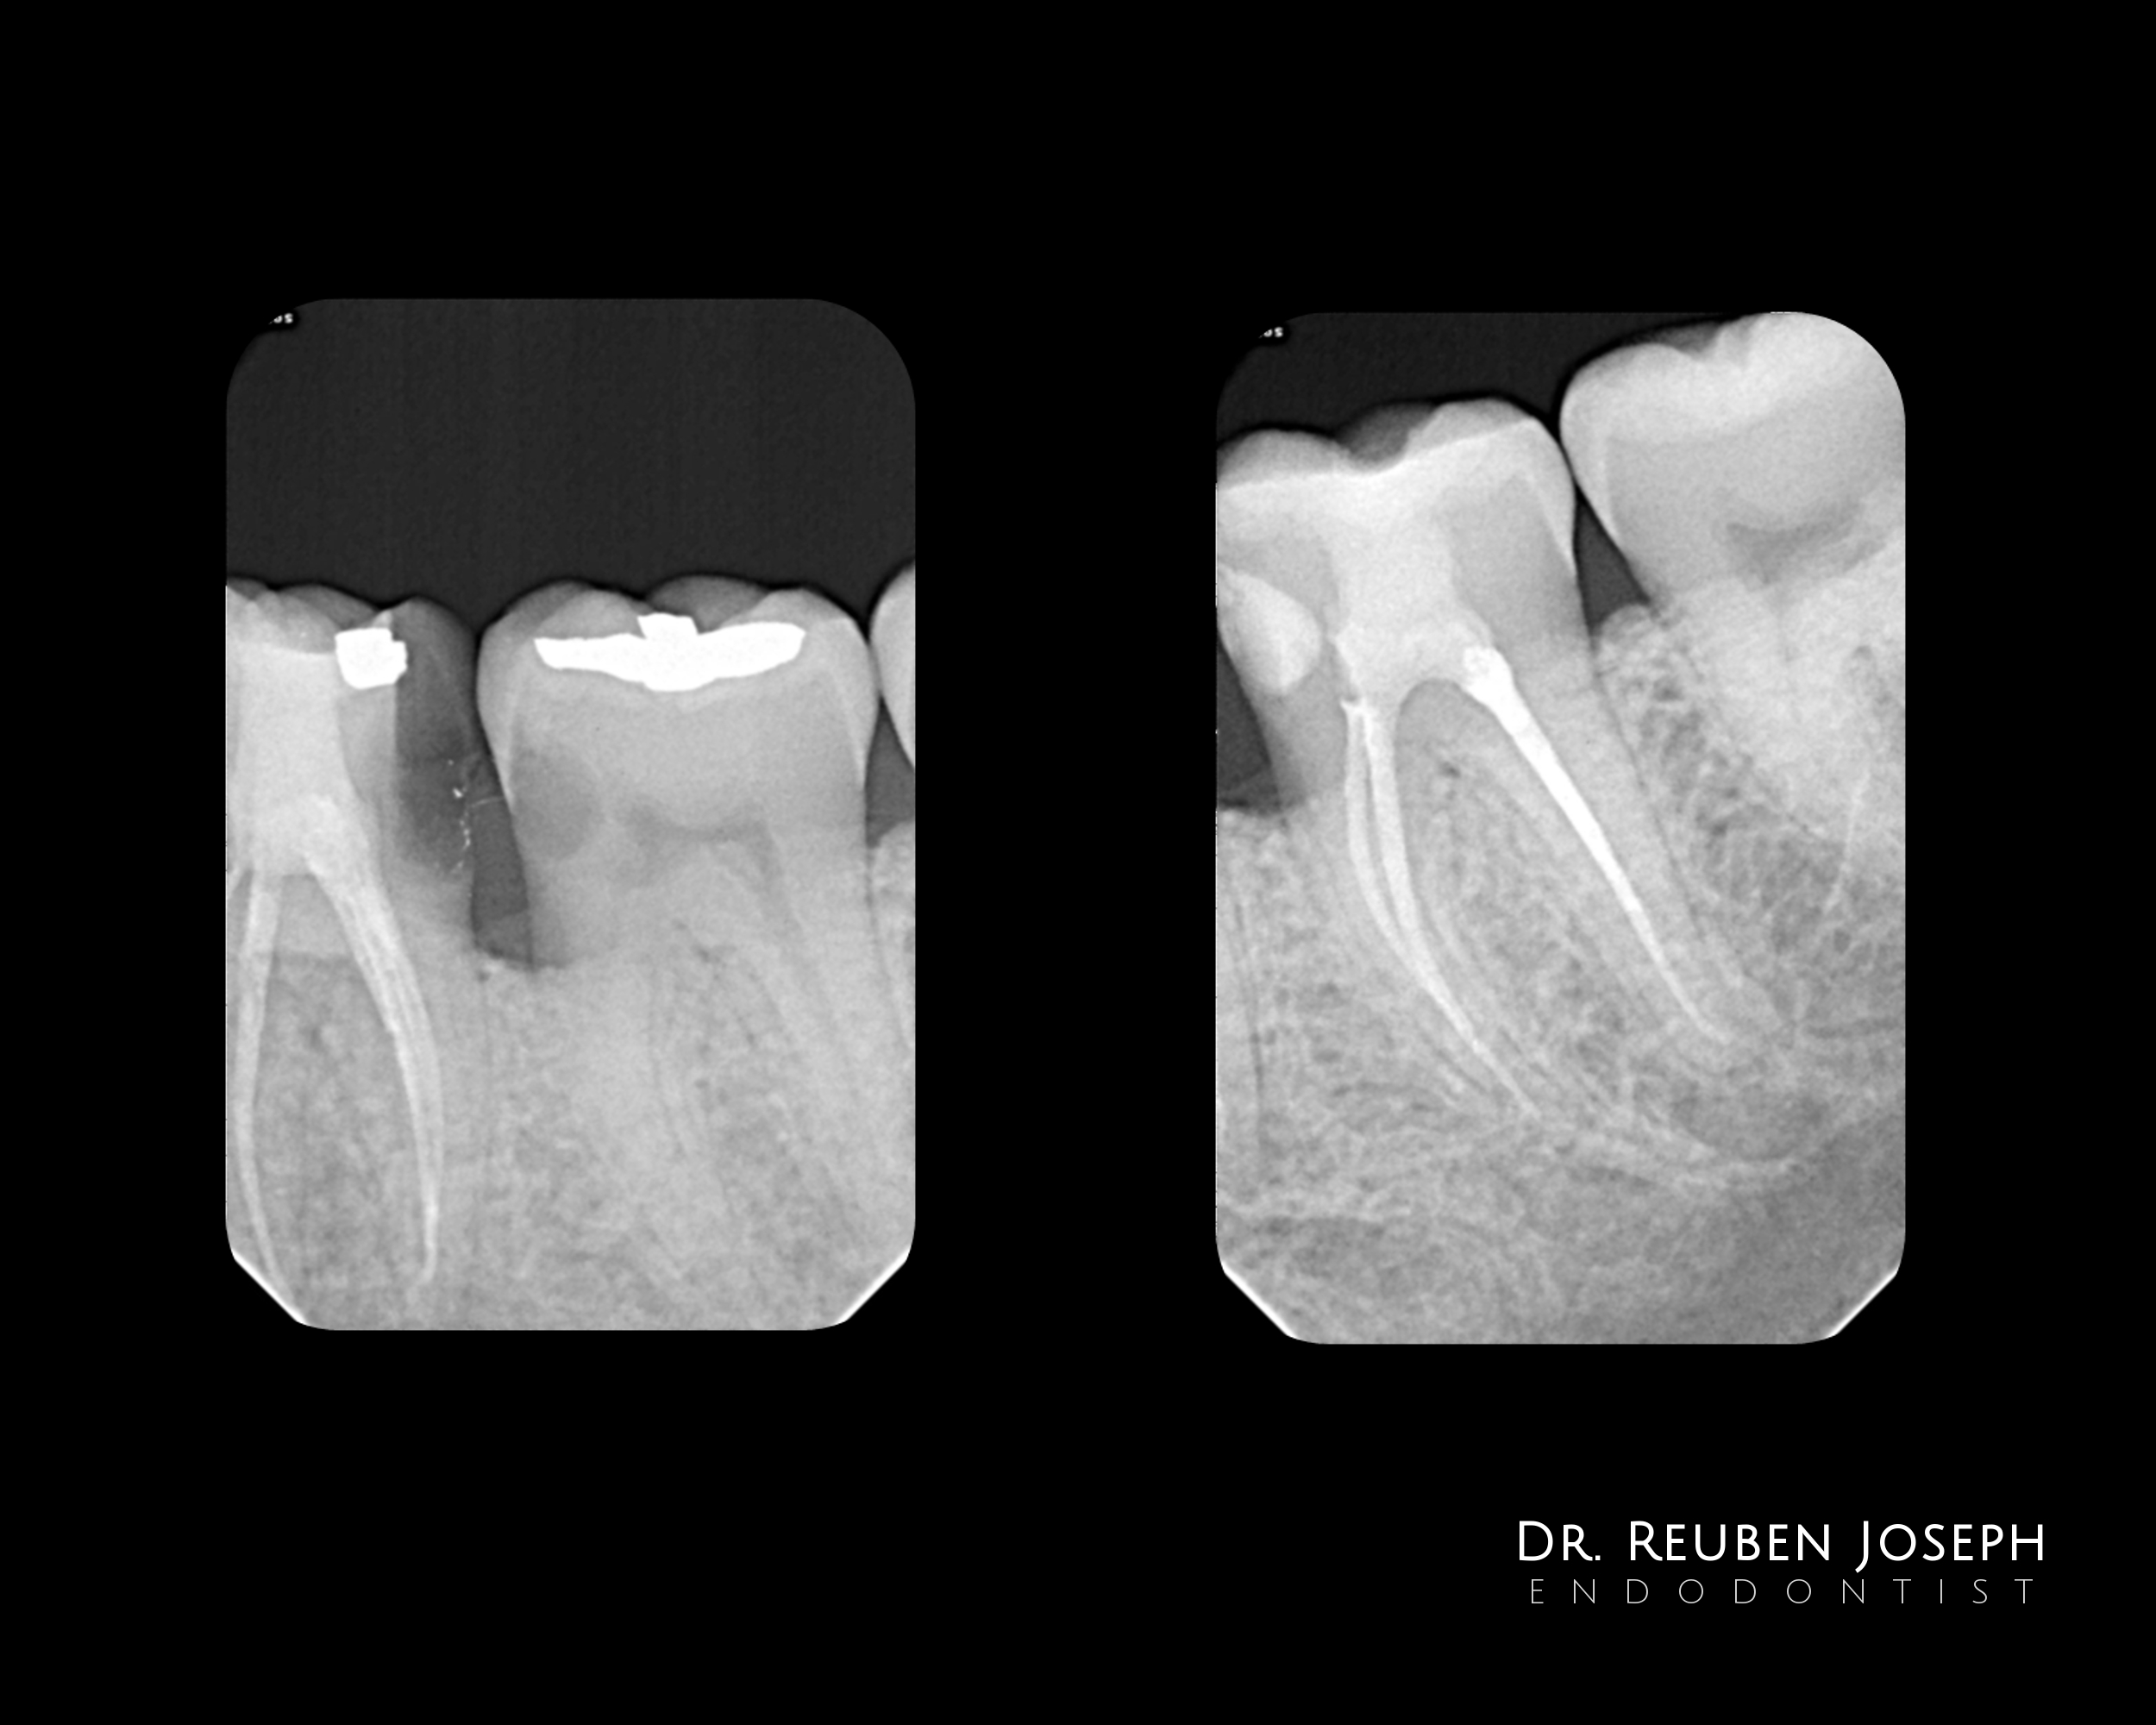

#18 RCT

With this kind of gingiva sinking the whole tooth an indirect post-endo would have been a nightmare (atleast for me) in this case. Orifice directed access done and the carious lesion prepared and restored separately along with the DO in the 19, the cuspal integrity is intact so just the direct composite post the endo.